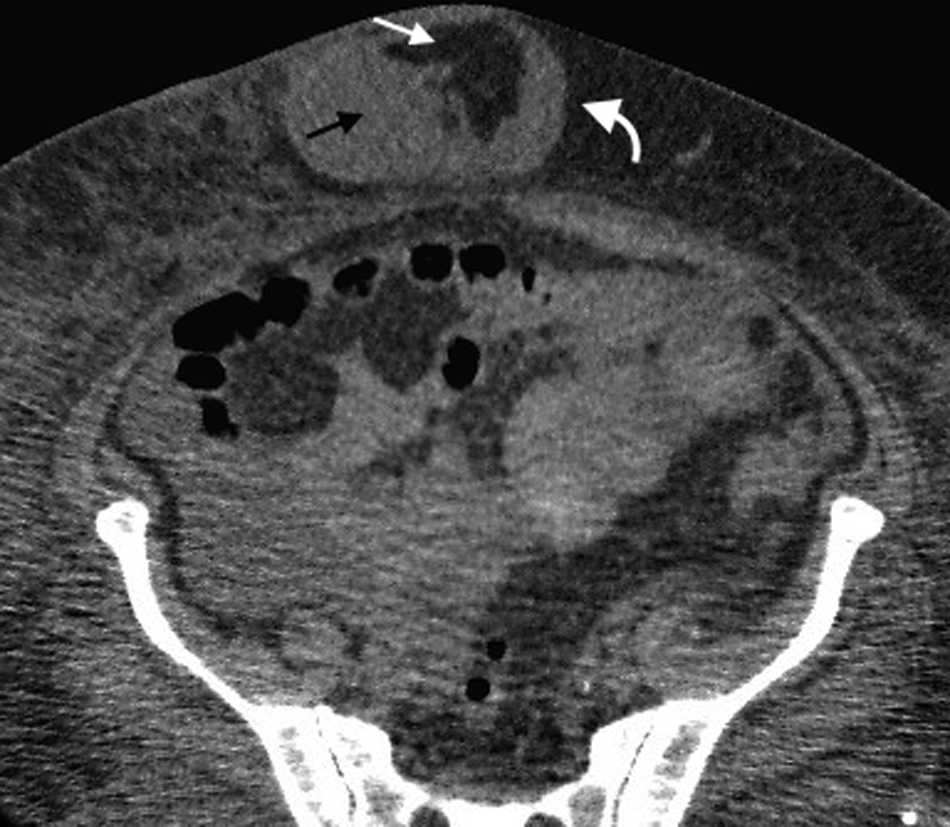

Eventraci??n

Representa una protrusi??n subcut??nea del contenido intraabdominal a trav??s de una zona debilitada de la pared abdominal o lumbar como consecuencia de una intervenci??n quir??rgica, una brecha posterior a un traumatismo cerrado o una malformaci??n cong??nita. Puede producirse en cualquier incisi??n quir??rgica sobre la pared abdominal, incluyendo los orificios de los trocares de laparoscopia. Es m??s frecuente en las incisiones verticales que en las transversales1.

La mayor??a se desarrolla durante los primeros 4 meses despu??s de la cirug??a, un per??odo cr??tico para la curaci??n de las capas musculares de la pared abdominal18. Se puede manifestar con signos y s??ntomas en su primer a??o, aunque un 5-10% permanece silente durante un per??odo prolongado hasta su detecci??n2.

Los estudios radiol??gicos pueden ser utilizados para visualizar los segmentos herniados y evaluar las complicaciones asociadas, tal como la obstrucci??n intestinal. Muchas veces se usan en evaluaciones dificultosas, como en pacientes de marcada obesidad o que tienen contenido herniario f??cilmente reductible o cicatrices de gran tama??o19 (figs. 12 y 13).